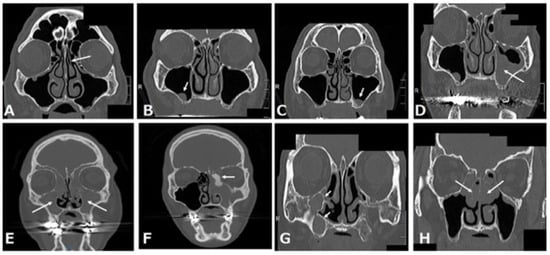

A systematic review indicated that a deviated nasal septum is associated with an increased prevalence of rhinosinusitis [11] because the curvature of the convexness of the nasal septum laterally displaces the middle turbinate and uncinated process, narrowing the ethmoidal infundibulum and reducing the ventilation and drainage of the maxillary sinus (Figure 4A).

2.3.2. Concha Bullosa or Paradoxical Middle Turbinate

Fadda et al. showed that anatomical variations in the middle turbinate, such as the concha bullosa and paradoxical middle turbinate, are associated with an increased prevalence of rhinosinusitis [12] because they laterally displace the uncinated process, narrowing the ethmoidal infundibulum and reducing ventilation and drainage of the maxillary sinus (Figure 4B).

2.3.3. Haller Cells

Haller cells are defined as infraorbital ethmoid cells. Haller cells also cause rhinosinusitis [12] because the presence of Haller cells can induce the stenosis of the ethmoidal infundibulum, consequently reducing the ventilation and drainage of the maxillary sinus (Figure 4C).

2.3.4. Accessory Ostium

The accessory ostium is located behind the maxillary natural ostium. Doctors should be careful not to confuse it with a natural ostium on computed tomography (CT) (left panel in Figure 4D). The natural ostium cannot be confirmed by nasal endoscopy, but the accessory ostium can be confirmed by endoscopy (right panel of Figure 4D). Although some doctors think that the accessory ostium might improve drainage of the maxillary sinus, it may pose a risk for maxillary sinusitis, because the presence of an accessory ostium can lead to chronic maxillary sinusitis by recirculation of mucus secretions, as well as a decrease in the drainage function of the maxillary sinus [13].

Figure 4. (A) Right nasal septal deviation (arrow); (B) left paradoxical middle turbinate (arrow) and left concha bullosa of the middle turbinate; (C) left Haller cell (arrow); (D) bilateral accessory ostium of the maxillary sinus (arrow in CT (left panel)) and right accessory ostium (arrow in nasal endoscopic examination (right panel)). This was originally published in Case Reports in Otolaryngology: Suzuki-Yamazaki, M.; Takahashi, K.; Takada, S.; Kato, Y.; Baba, Y. “A successful treatment regimen for the prevention of sinusitis after maxillary sinus floor elevation surgery in a high-risk case.” Case Rep. Otolaryngol. 2020, 2020, 6869805 [16].